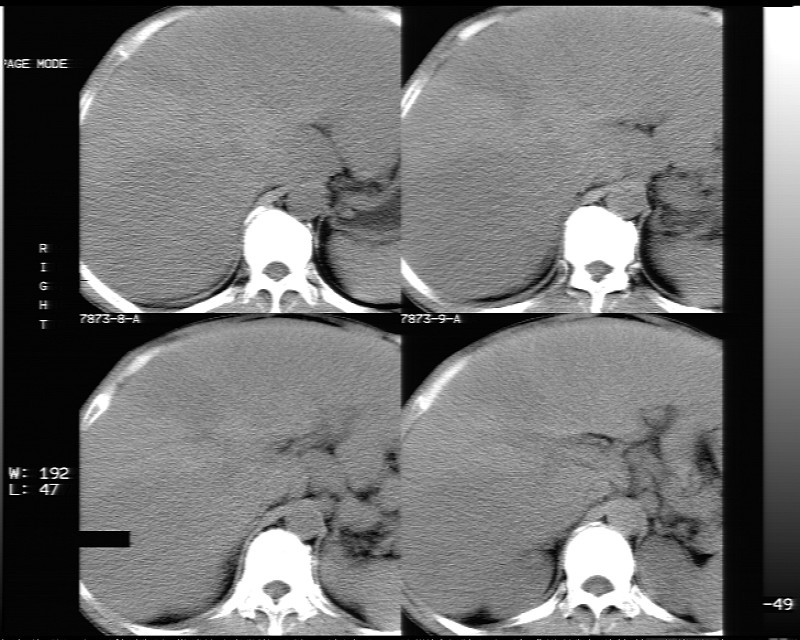

平扫示:

不均匀性脂肪肝

非均质性脂肪肝。

支持脂肪肝【无占位性,高低密度区同期强化,平扫与强化的密度成比例】

不均匀性脂肪肝。肝脏体积稍大,不除外合并肝功能损害。

1、不均匀脂肪肝;2、布加氏综合症(肝脏肿大,门脉纤细,下腔海绵状变性,肠系膜上静脉显著扩张)。